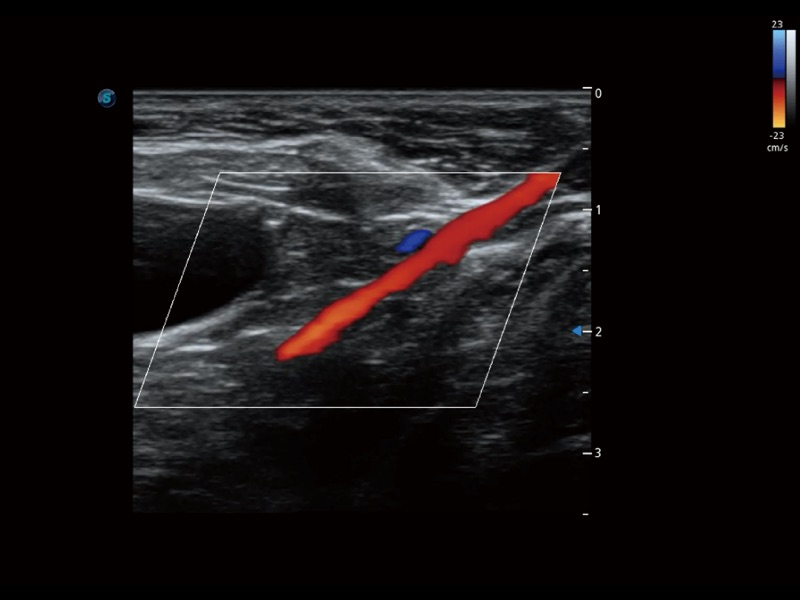

通過(guò)創(chuàng)新的 Matrix E自適應(yīng)濾波器和超長(zhǎng)時(shí)間域算法,極大提升超低速微細(xì)血流的檢出能力,同時(shí)更精準(zhǔn)地濾除軟組織和噪聲信號(hào),為獸用醫(yī)生提供以往無(wú)法通過(guò)常規(guī)血流獲得的疾病診斷信息。

通過(guò)色彩血流和實(shí)時(shí)寬景相結(jié)合,可觀(guān)察到完整的靜脈或動(dòng)脈的血流,方便醫(yī)生檢查。實(shí)時(shí)掃查過(guò)程中,如有任何操作失誤也可以很容易地進(jìn)行回掃擦除,而不會(huì)中斷掃查。